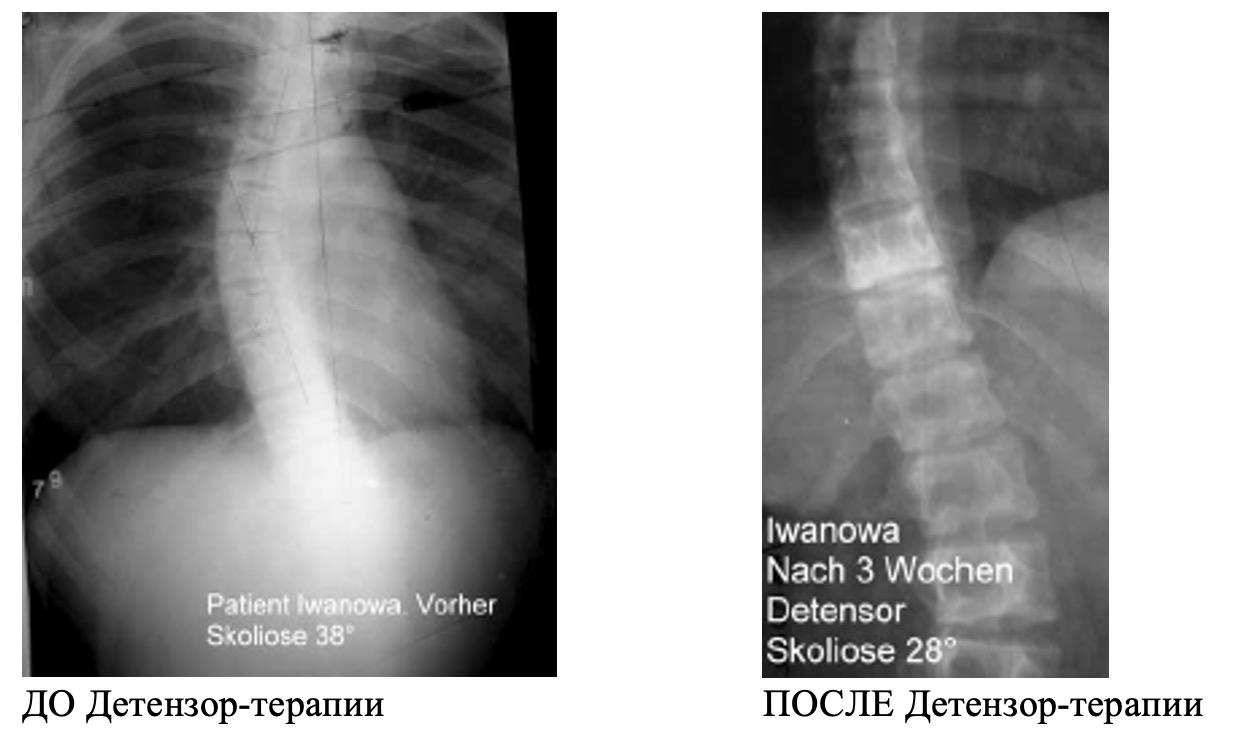

Из 13-ти обследованных больных с наследственными заболеваниями, сопровождающимися поражением опорно-двигательного аппарата и низкорослостью. У всех имелись выраженные изменения в позвоночнике, как проявление основного заболевания – кифозы, кифосколиозы, сколиозы (рис. 18). После окончания курса Детензор-терапии через 4 недели от начала лечения, при повторном измерении роста, зафиксировано его увеличение у 5 детей, составившее от 1 до 3,5 см. У всех больных наблюдалось улучшение осанки, уменьшение болей в позвоночнике.

Рис. 18. Результат применения Детензор-терапии при сколиозе

На рисунке видно, что после применения Детензор-терапии отмечено уменьшение степени сколиоза: с 3-ей степени (38°) до 2-ой степени (28°), увеличение межпозвонковых дисков.